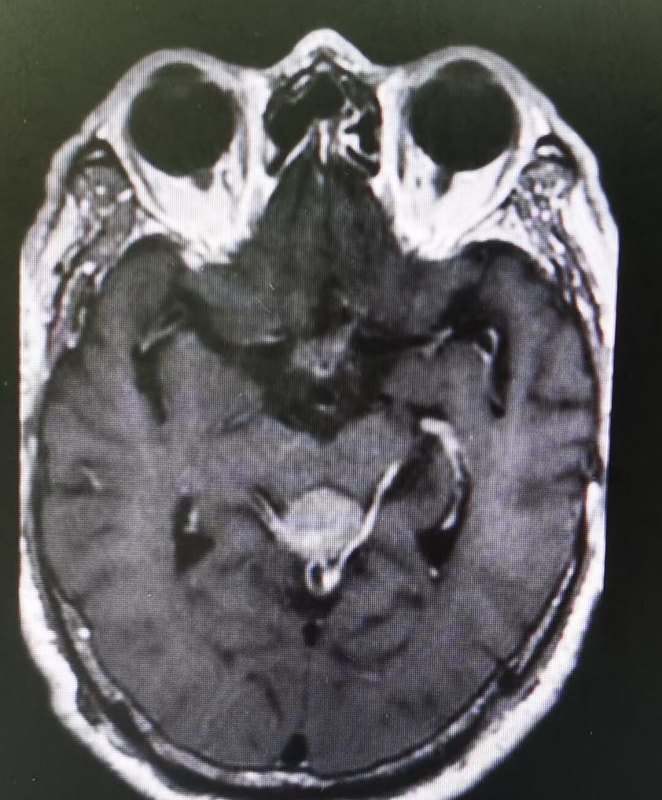

治療前男,9歲,因頭痛伴惡心嘔吐20余天入院。入院查體:神清,急性病容。頭部磁共振顯示:松果體區(qū)占位。抽血查HCG正常,血AFP18.52nh/ml(0-2.00)術(shù)前診斷考慮:松果體區(qū)占位:生殖細(xì)胞腫瘤可能性大。梗阻性腦積水。治療中經(jīng)兒童腦腫瘤多學(xué)科討論后認(rèn)為可以直接手術(shù)切除。遂實(shí)施開顱手術(shù)切除病變。手術(shù)采用經(jīng)幕下小腦上入路,顯微鏡下全切除病變。病理為混合生殖細(xì)胞腫瘤。術(shù)后建議輔助治療。出院時(shí)神清語(yǔ)利,四肢活動(dòng)好。治療后治療后6月恢復(fù)良好。完成放射治療。頭部及全脊柱脊髓磁共振掃描未見復(fù)發(fā)。